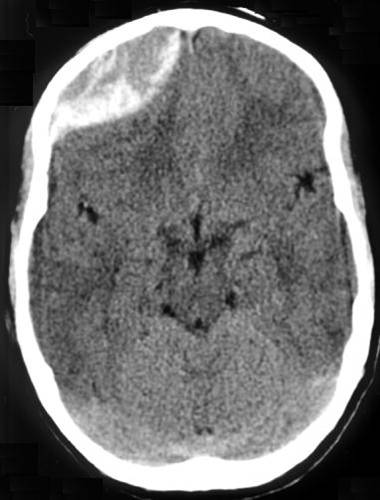

- Subdural Hematomas: Occur when there is bleeding into the space between the dura and arachnoid membranes. They appear as concave or crescent-shaped collections of blood on CT scan and can cross suture lines. These are generally caused by tears to the bridging veins between the cortex and venous sinuses. The hemorrhage occurs more slowly than in epidural hematomas, although still over a period of a few hours.

Figure: Subdural hematoma. Image courtesy of Dr. James Heilman. Image used under the Creative Commons Attribution-Share Alike 3.0 Unported license.